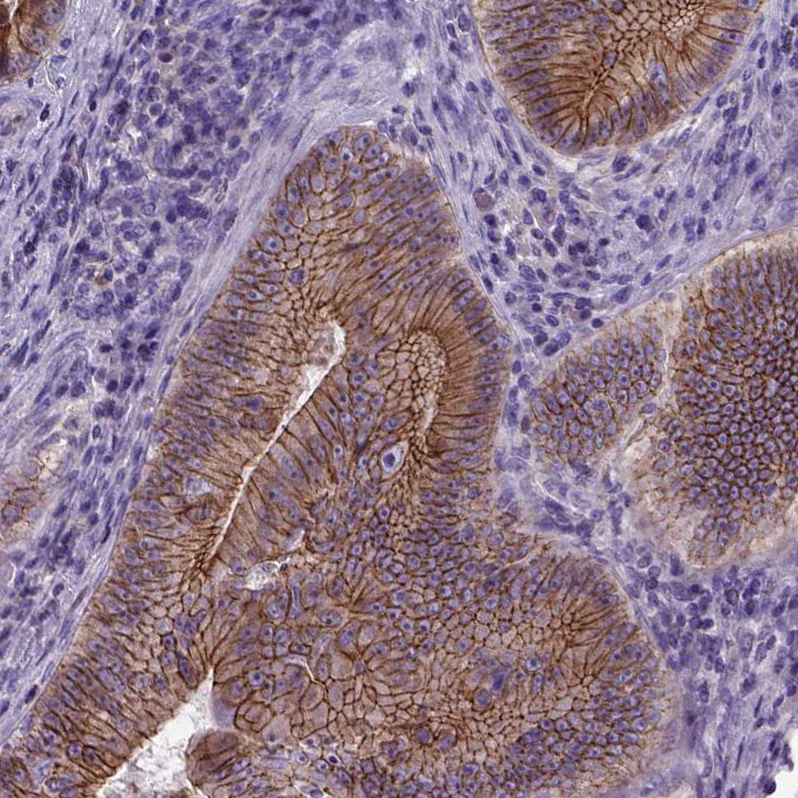

Immunohistochemistry analysis in human duodenum and cerebral cortex tissues using AMAb90865 antibody. Corresponding CDH1 RNA-seq data are presented for the same tissues.